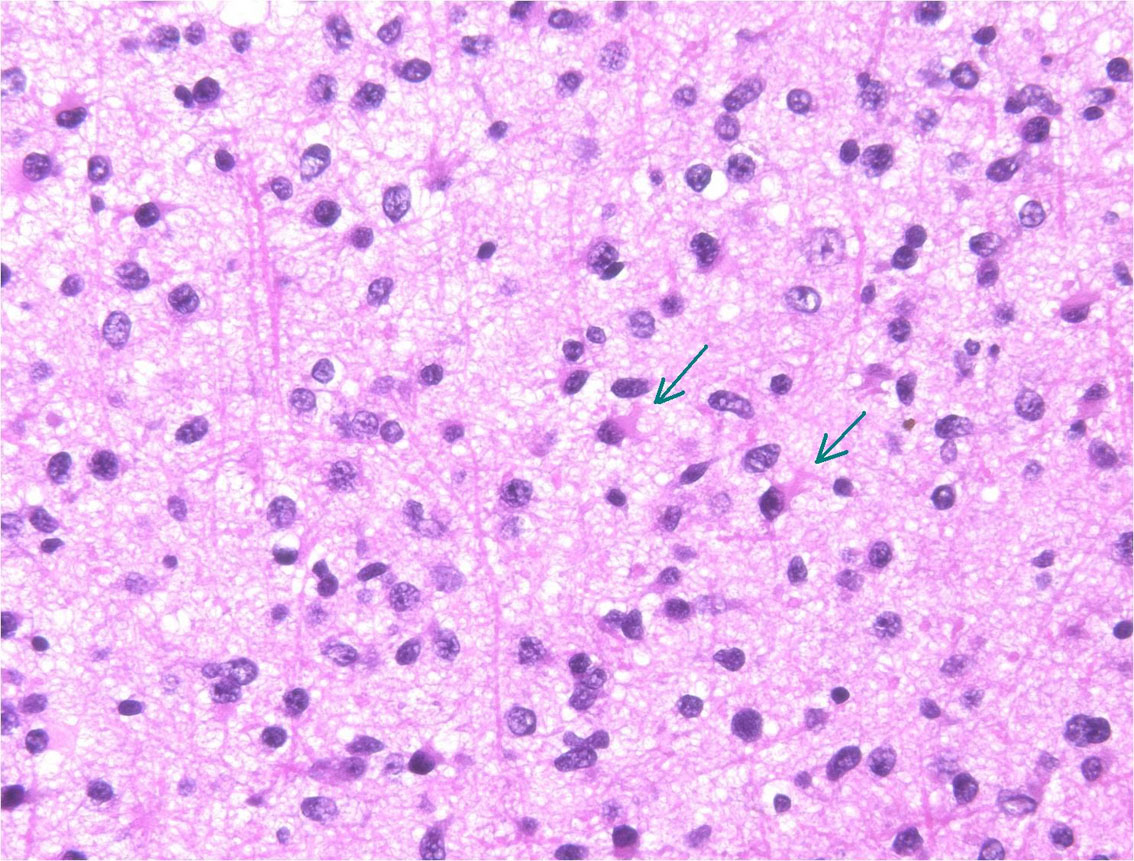

病理は,星細胞に特有の胞体を有しグリア線維が明瞭なびまん性星細胞腫です(クリックすると拡大で見えます)

Ki-67という抗体を使った免疫組織染色でMIB-1 indexというものを見ます。平均で2.5%くらい,高くても4%です。それ以上はグレード3の可能性が高くなります。左の写真のMIB-1の染色率 labling index は3.5%くらいで,グレード2のびまん性星細胞腫としてはやや高い値です。MIB-1染色率が高くなると悪性度が高い傾向にあると考えられます。